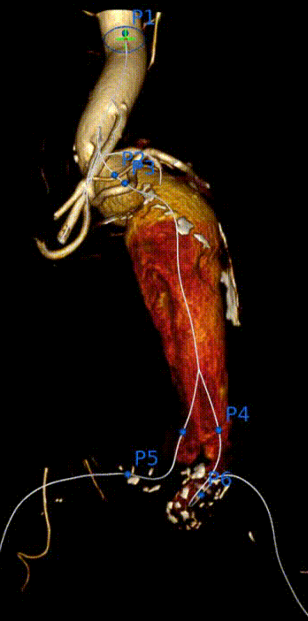

3D打印技术

窗口区域置于降主动脉平直段,远离扭曲瘤颈段

(高于内脏分支开口区),以利于各窗口的超选

3D打印

3D打印技术:帮助解决支架体外精准开窗问题。

3D打印技术的技术流程